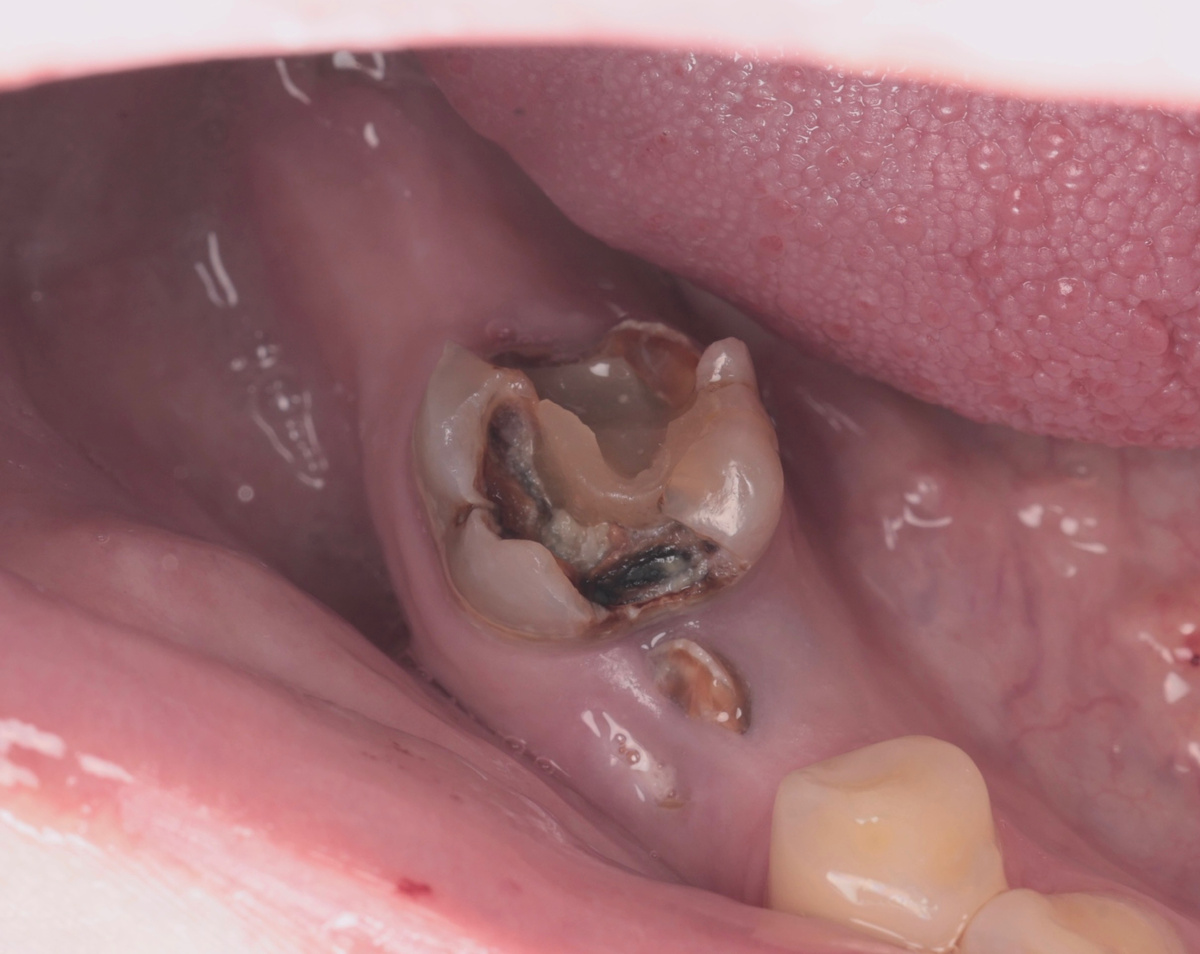

История терапевтическя не закончилась и пациент приехал снова. На этот раз его и нас ждал, пожалуй, самый интересный зуб из всех:

Разрушенный 4.6 зуб

Если бы этот зуб пришёл на кастинг в фильм зубных ужасов, его бы взяли без промедления. Настоящая развалина, будем честны - и на вид, и по факту.

4.7 уже удалили за месяц до приезда. И вот стоит одинокий, разрушенный 4.6 с периодонтитом, каналы его выглядят пустыми, коронковую часть "пожрал" кариес.

Стенки родные тонкие. Стенок мало. В каналах - цинкоксидэвгенольный цемент (кто знает - тот поймёт, удовольствие ещё то его оттуда доставать).

Казалось бы - зачем мучиться? Удалить да и поставить мост на имплантатах. Быстро, понятно, предсказуемо.

Но Роман Юрьевич так не работает. Он смотрит глубже - ортопедический прогноз хороший, эндодонтическое лечение технически выполнимо, все показания к сохранению зуба есть. А если зуб можно спасти - его нужно спасать.